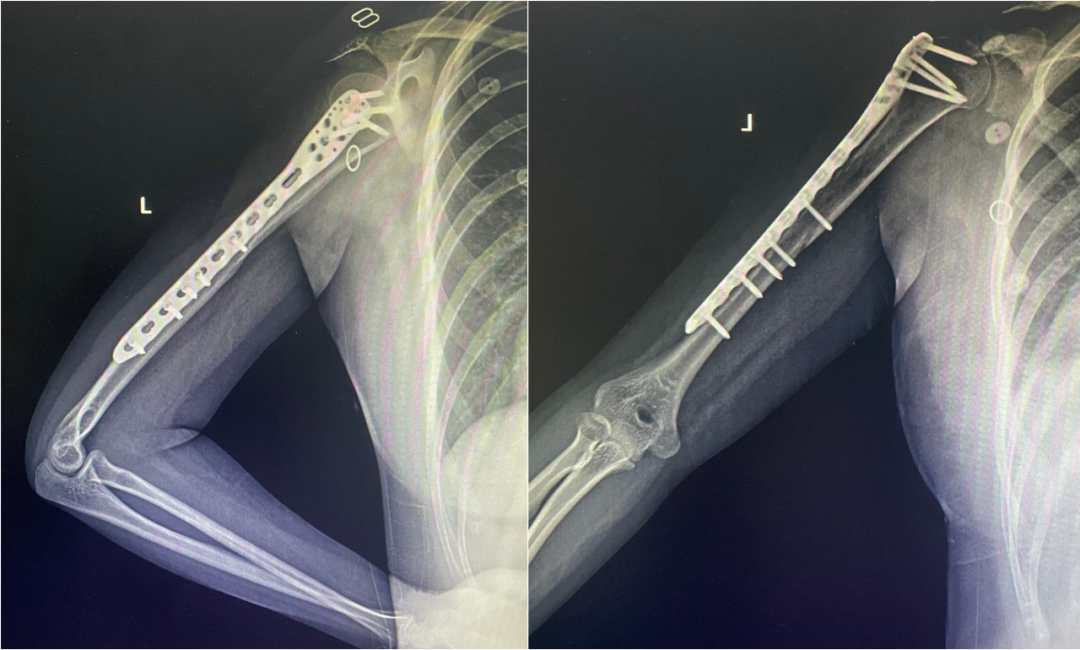

钢板固定